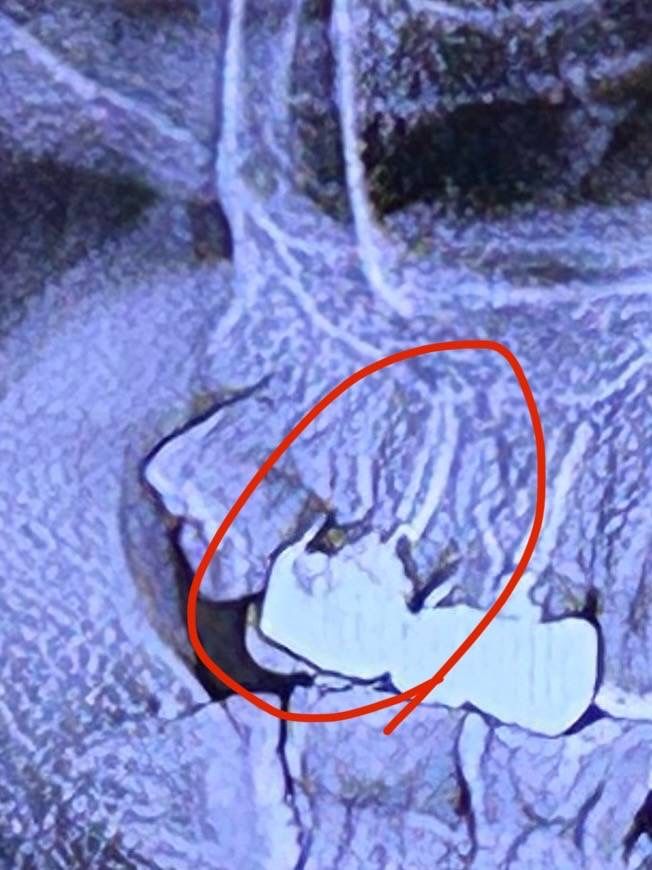

신경치료한 부분 충치는 크라운 열어봐야만 아나요?

신경치료한 a병원에서는 충치가 아니라 각도상 검게 보일뿐이다하고

B병원에서는 심한 충치다 라는데

확인해 볼 방법은 크라운 열어보는 수 밖에 없나요?

24년 5월에 치료했고 사진은 11월에 촬영한 것입니다

방사선 사진으로 봤을 경우에는 충치가 크게 있어 보입니다. 일단은 크라운을 제거해 보는 것이 정확합니다. 충치가 있다면 충치를 치료할 수 있지만 충치가 치조골 아래로 내려가게 되면 치아를 발치해야 할 수도 있습니다.

사진상으로 보면 안쪽에 충치가 많이 진행된 상태같습니다. 정확한건 크라운을 제거해보셔야될것같긴합니다.